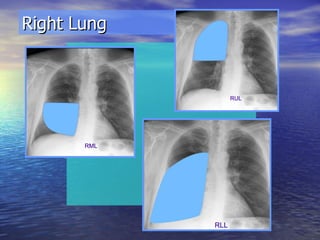

Right Lung

Right Lung Bronchogram